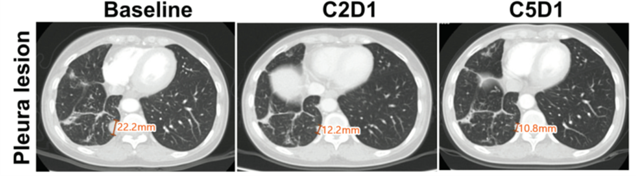

보로노이는 이번 AACR2025를 통해 임상 1a상 용량 증량 단계 진행 중에 EGFR C797S 이중 돌연변이(EGFR L858R/C797S) 뇌전이 환자에게 저용량인 40mg를 투약하여 부작용 없이 폐 병변에서 50% 이상의 부분관해를, 뇌 병변에서 완전관해 반응을 확인하였다고 공개했다.

구체적으로는, 22.2mm의 폐에 있던 종양이 2개월 투약 후, 50% 이상 크기가 감소하였고, 뇌에 있던 병변은 10.6mm의 종양은 4개월 후 완전히 사라진 것을 확인했다.